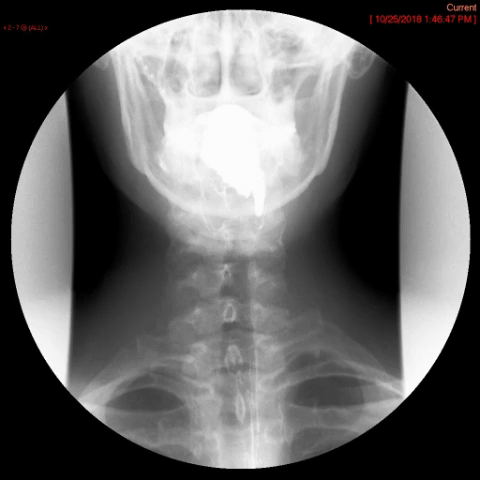

- Method—Cervical:

- Repeat steps 4-7 with the patient in the AP position

(key image 3)

(key image 4).

- Cervical images are obtained in the lateral and AP projections as the patient swallows thick barium.